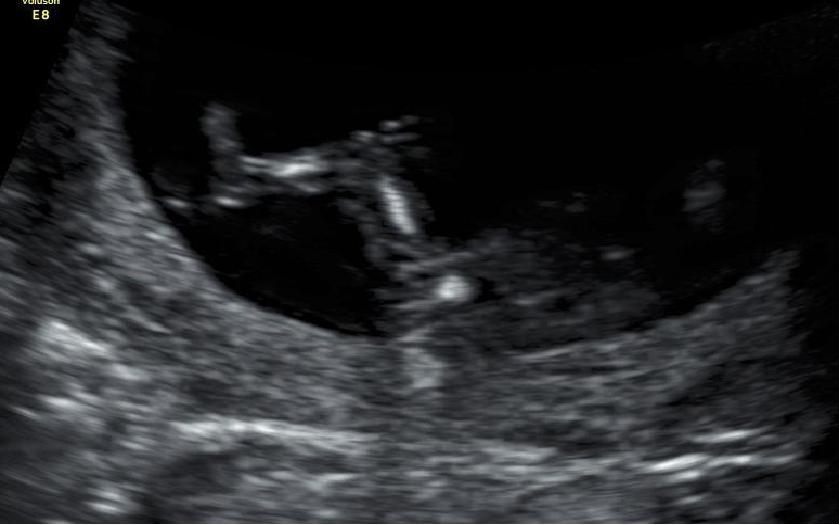

Attachment 17204Am i having a boy or girl? Please tell me what you think :)

These ultrasounds were taken at 12 weeks excatly :) :)

At 12 wks potty shot isn't reliable. Leaning girl based on other shots but it's still early and nub could possibly rise xx